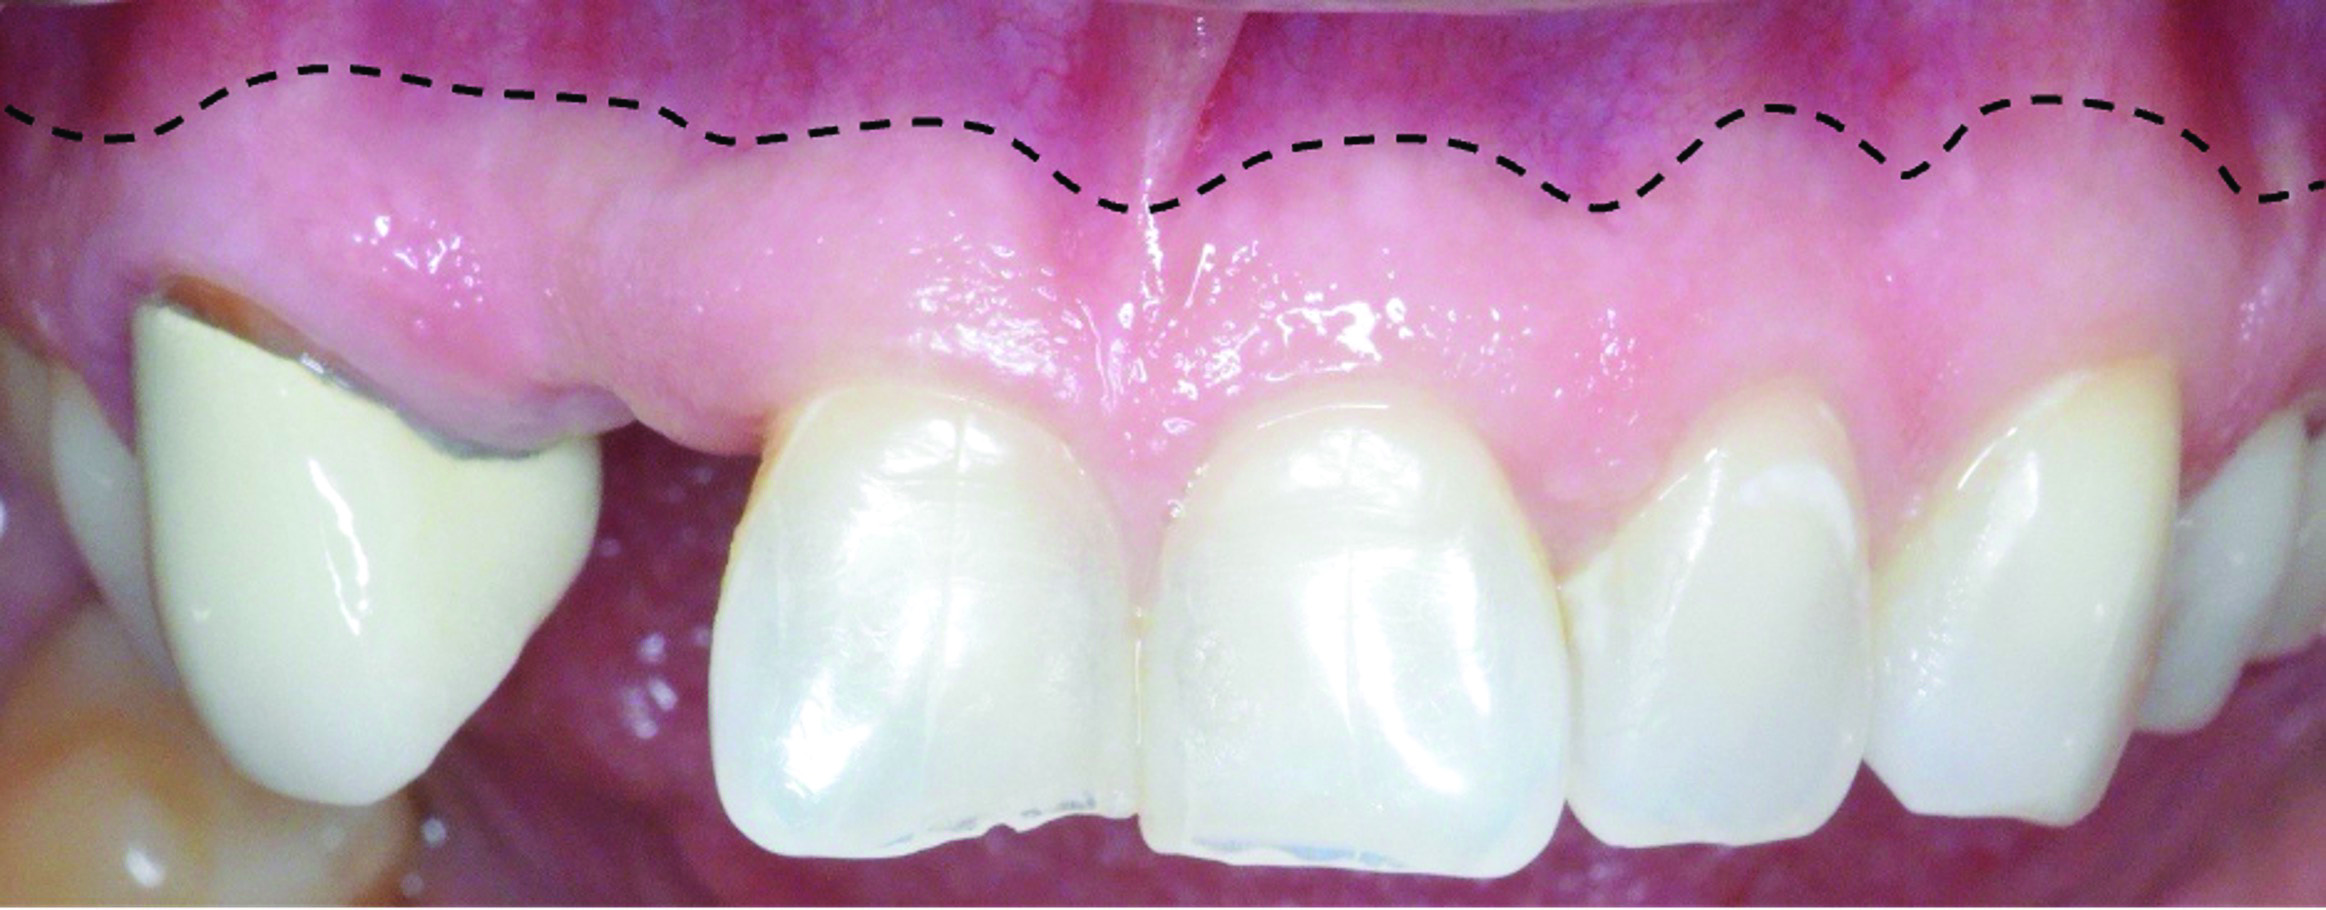

Fig 6 through Fig 8. Example of increasing KMW with an APF at implant uncovery. Fig 6: initial presentation showing lack of KMW; Fig 7: healing abutment placement with APF; Fig 8: 2 months post-treatment. (The dotted lines indicate the MGJ.) Fig 9 through Fig 11. Example of increasing KMW with an APF and FGG at implant uncovery.

Fig 9: initial presentation;

Fig 10: healing abutment placement with FGG; Fig 11: 2 months post-treatment.

Fig 11: 2 months post-treatment.